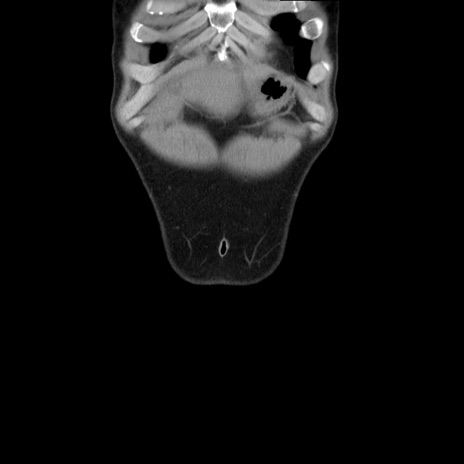

横断像

症例36(冠状断像)

【症例】20歳代 男性

【主訴】心窩部痛

【現病歴】今朝より上腹部痛あり。一旦軽快していたが再度出現したため救急要請。昨日夕に白身の魚を含む刺身を食べた。

【身体所見】BP 136/89mmHg、HR 74/min、BT 37.0℃、腹部:膨満、軟、心窩部に圧痛あり。反跳痛なし、筋性防御なし、腸雑音やや亢進あり。

【データ】WBC 17700、CRP 0.48